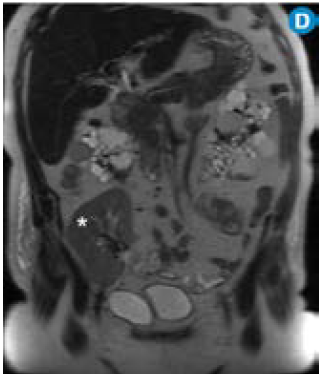

Por su alta sensibilidad, disponibilidad y bajo costo, la ecografía renal es el estudio inicial con el que se pueden observar riñones grandes con quistes bilaterales, múltiples y tamaño variable (figura 1); sin embargo, es altamente dependiente del operador y es menos sensible para detectar quistes <1cm que se visualizan mejor en la escanografía o en la resonancia magnética 24. Pese a que en la actualidad no existen criterios estandarizados en estas dos técnicas imagenológicas para el diagnóstico de la PKD, la tomografía computarizada (TC) y la resonancia magnética (RM) son más sensibles para el diagnóstico de los quistes en los casos dudosos, la detección de complicaciones, la valoración de la progresión y la respuesta al tratamiento 25 (figura 2).

En la ARPKD, el diagnóstico puede ser realizado en el período intrauterino, neonatal o en los primeros meses de vida por medio de una ecografía renal en la que se observan los riñones aumentados de tamaño, con pérdida de la relación corticomedular, hipoplasia pulmonar y oligohidramnios debido al bajo gasto urinario 31. En edades posteriores se prefieren las imágenes por TC y RM para seguimiento o, como ya se mencionó, para casos dudosos. En las fases tempranas, los riñones pueden ser de tamaño y forma normal; en las fases posteriores aumenta el número y el tamaño de los quistes, con distribución difusa del parénquima, aumento del tamaño (se alcanzan longitudes de hasta 40cm) y, por consiguiente, aumento del volumen renal. La RM es la técnica de elección empleada para la volumetría de los quistes y del parénquima como indicadores de progresión o de respuesta al tratamiento.